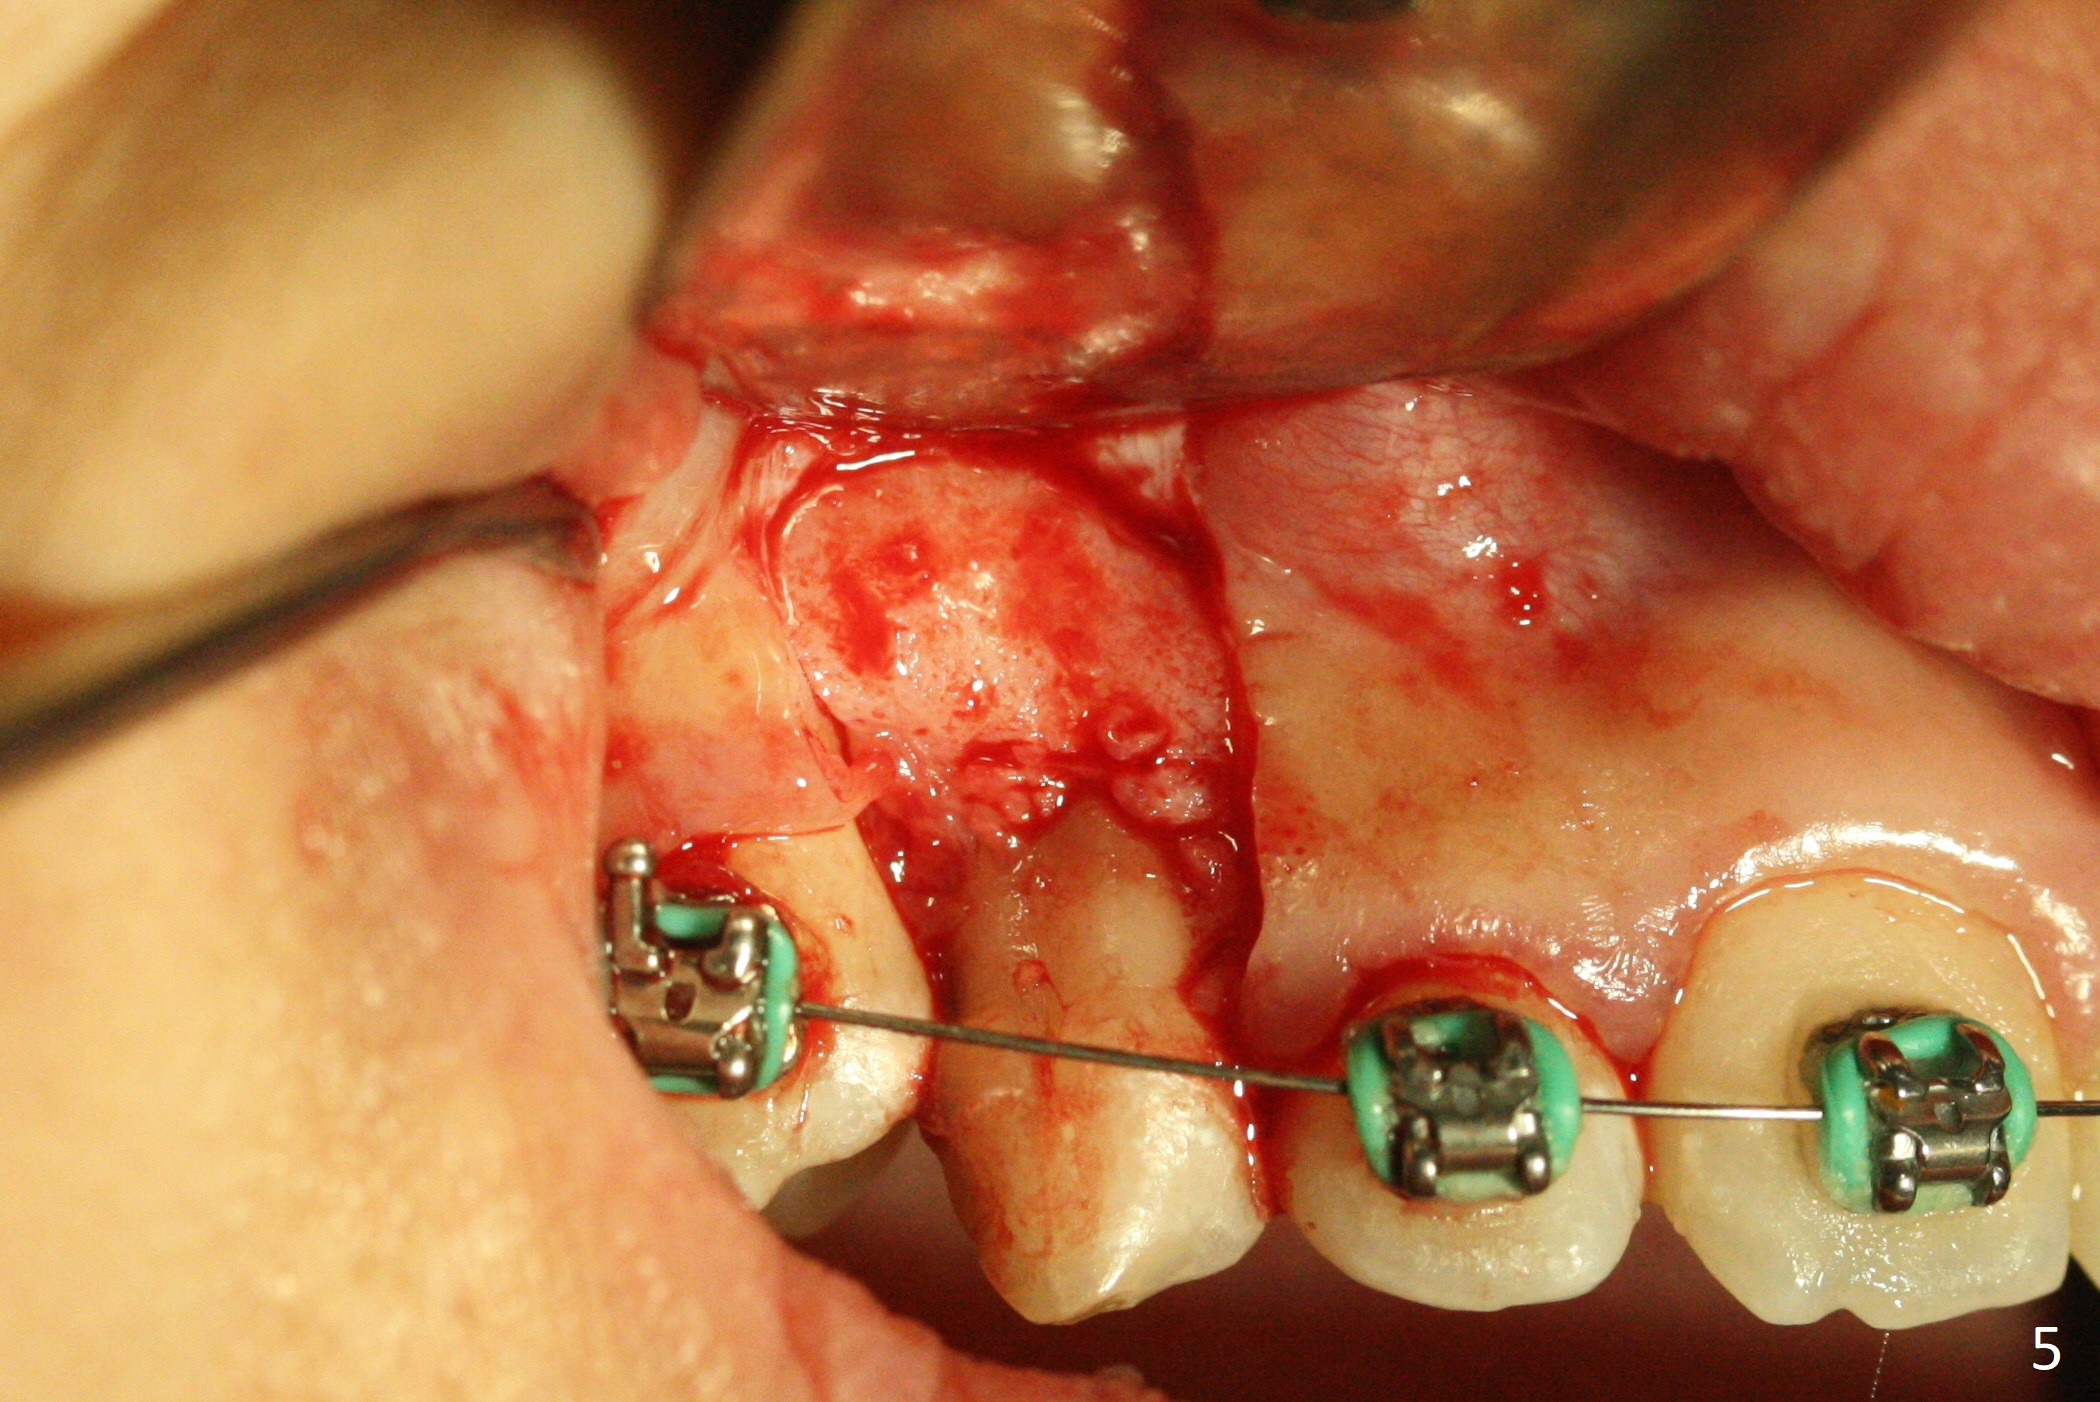

A 13-year-old woman has an impacted canine (Fig.1 (6)) and retained deciduous one (C). After initiation of orthodontics, she returns for surgical access to the impacted canine and placement of device to facilitate eruption (Fig.2,3). Incision is made buccal (Fig.4), but there is no tooth buccal (Fig.5). Extraction of the deciduous canine does not reveal the impacted one (Fig.6), but there is palatal elevation (*). Palatal access shows the impacted tooth (Fig.7) and allows placement of a retraction device (Fig.8). Careful clinical exam and CBCT are necessary diagnostic steps.